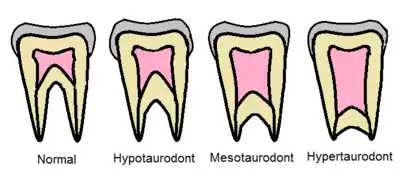

One of the first attempts to classify taurodontism was made by C.J.Shaw.[4] He used the apical displacement of the pulp chamber floor to classify taurodontism into four distinct categories: cynodont (normal), hypotaurodont, hypertaurodont, and mesotaurodont.

Earlier classification systems considered only the apical displacement of the pulp chamber floor; whereas, later systems additionally consider the position of the pulp chamber in relation to the cemento-enamel junction and alveolar margin.[3]